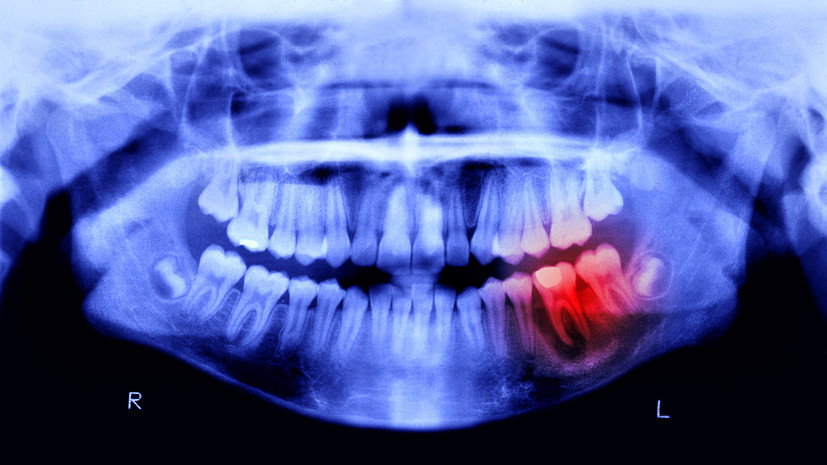

В беседе с aif.ru эксперт отметила, что основной причиной появления боли в зубах является кариес, который разрушает эмаль зуба.

Болеутоляющие препараты на этой стадии уже практически бессильны, так как болезнь распространилась глубоко и проникла в пульпу зуба, добавила Шелудкова.